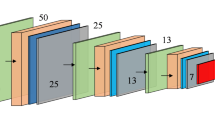

Lung cancer is one of the most common cancers in the world, and the detection and classification of benign-malignant lung nodules are critical during the diagnosis and treatment for lung cancer. In this paper, a multi-view improved dense convolutional network is proposed for the classification of benign-malignant pulmonary nodules, where more information of input multi-scale features can be extracted from 2D views of nine different directions. The improved dense block and other layers are linked by shortcuts, which optimizes the feature extraction. The proposed network model is trained in the LIDC-IDRI dataset, and the results show that the average classification accuracy and AUC are 86.52% and 97.23% respectively, which means that the network model has significantly improved the performance of benign-malignant pulmonary nodules classification.

Shen, LH., Wang, XH., Gao, MX., Li, B. (2021). Classification of Benign-Malignant Pulmonary Nodules Based on Multi-view Improved Dense Network. In: Huang, DS., Jo, KH., Li, J., Gribova, V., Bevilacqua, V. (eds) Intelligent Computing Theories and Application. ICIC 2021. Lecture Notes in Computer Science(), vol 12836. Springer, Cham. https://doi.org/10.1007/978-3-030-84522-3_48